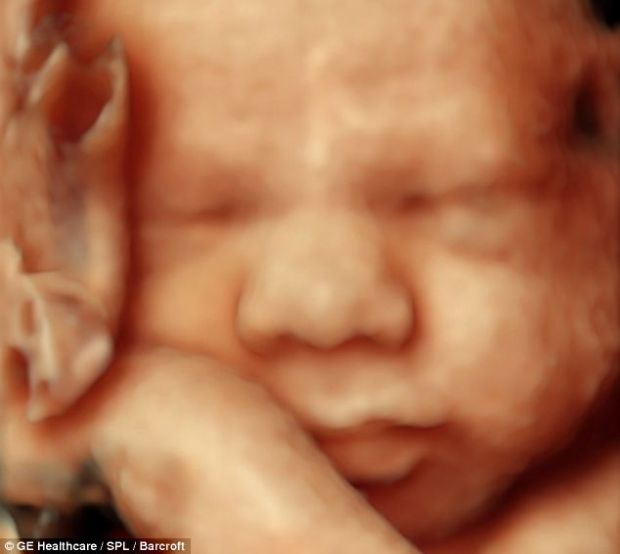

DOWN SENDROMUNDA ULTRASON BULGULARI Jinekoloji Gebelik

Anne Karnındaki Bebek Görüntüleri